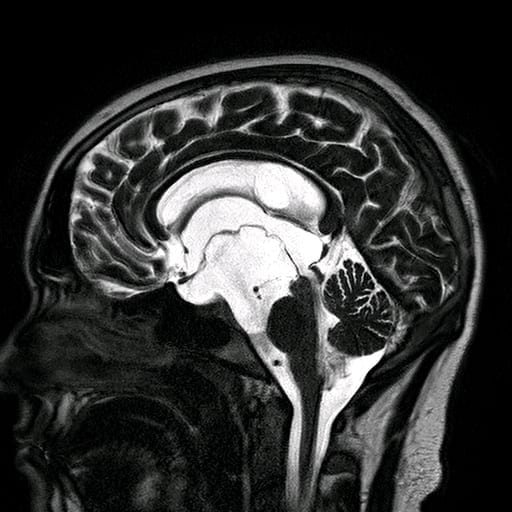

A 45-year-old patient presented with left foot pain for 10yrs. Investigations of the foot itself had found no cause for the pain. An MRI of the calf (Fig 1) showed a lesion of the tibial nerve. Palpation of the calf at the site of the lesion reproduced the foot pain, and she was scheduled for surgery.